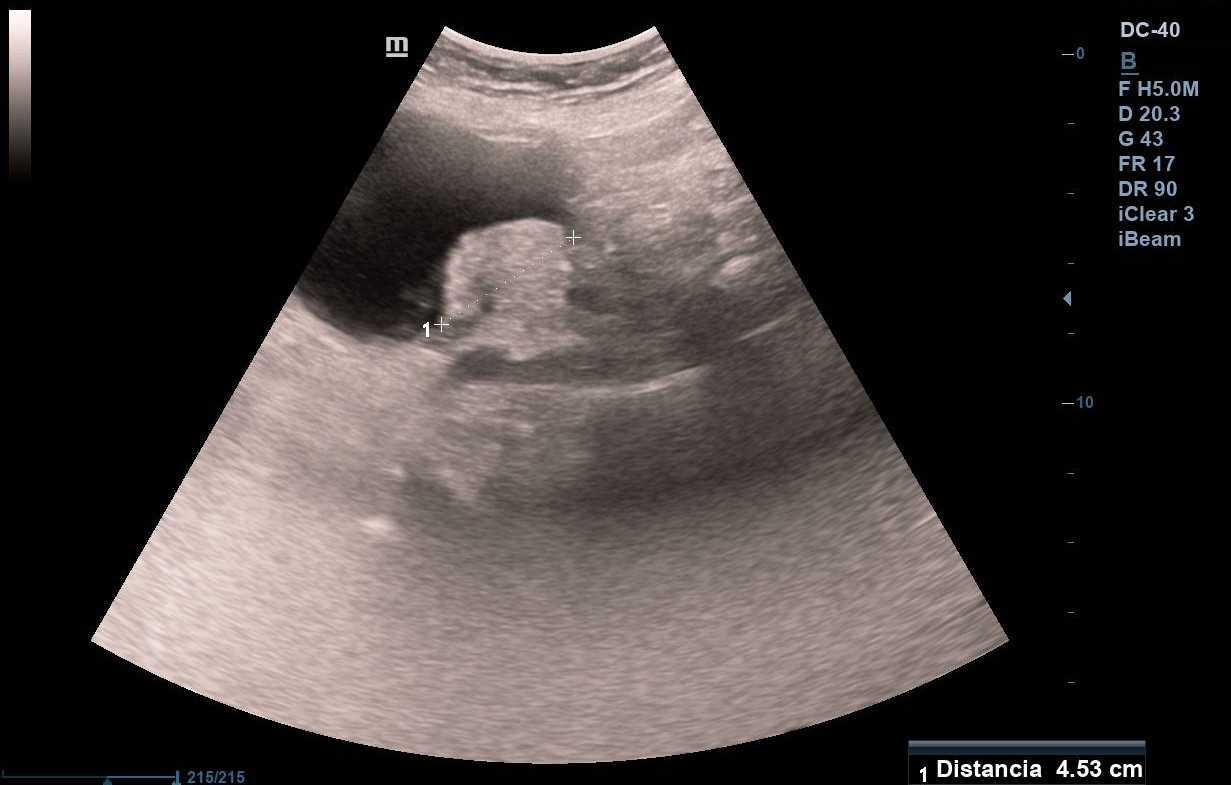

Paralelamente realizamos una nueva ecografía en Atención Primaria con intención formativa, objetivando entonces de manera inesperada que la vejiga, bien replecionada, no presenta lesiones en su interior. Por el contrario, al bascular el transductor se observa una tumoración dependiente de ovario izquierdo, que, sin valorar adecuadamente la proyección, podría parecer ser intravesical.

La paciente consulta en enero de 2022 por molestias abdominales siendo la exploración normal, por lo que se solicita una ecografía abdominal reglada que se demora 4 meses. En ella el radiólogo describe «una tumoración sólida de 5 cm de base por 2,5 cm de proyección intraluminal en la cara posterolateral izquierda vesical, de contornos muy homogéneos. Podría tratarse de un leiomioma de la pared vesical, pero no se puede descartar tumoración transicional agresiva».

Adenocarcinoma de colon metastásico. Resección de metástasis de adenocarcinoma enteroide de 5 x 4 cm sobre cistoadenoma seroso en ovario izquierdo.